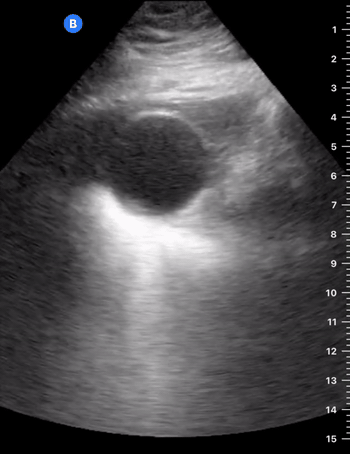

Classically, GB calculi are described as intraluminal hyperechoic images that cast posterior acoustic shadows. If not impacted, they should also be mobile and have gravitational dependence. Consequently, scanning the patient in more than one position may elucidate an impacted gallstone, as it will not move with gravity. Neither a very small stone (<5 mm diameter) nor sludge will cast a posterior shadow, although multiple small calculi (microlithiasis) may present poorly defined shadowing.

WALL ECHO SHADOW

If the gallbladder is completely filled with stones, the normal fluid-filled structure with posterior enhancement is no longer seen. Instead, the wall echo shadow (WES) sign can be found as two parallel bright lines with a large posterior shadowing. The bright line closest to the probe is the GB wall and the line beneath represents the echogenic calculi. WES is important because it may be misinterpreted as a bowel loop, when in fact represents cholelithiasis.